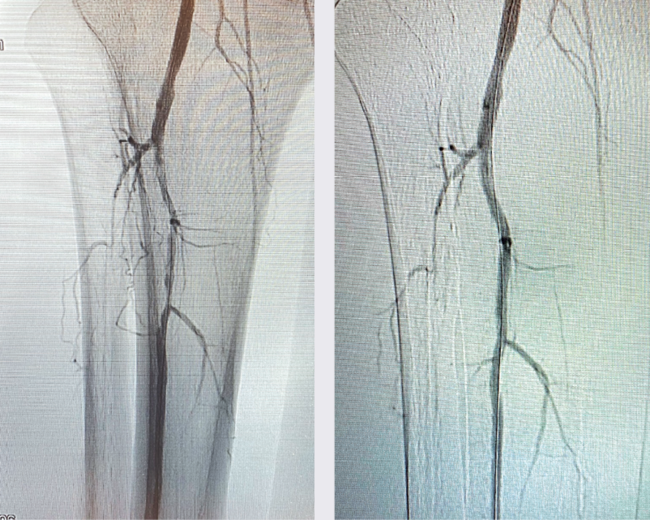

This is a white, male smoker in his mid 40s.  The patient has smoked 2 packs a day for the past 27 years, and has a past medical history significant for hypertension and type 2 diabetes. The patient was referred to my office with a non-healing left great toe ulcer. He had been previously evaluated and treated by his cardiologist four months prior for the same complaint. The cardiologist performed a left lower extremity arteriogram and intervention. He attempted to cross the chronic total occlusion (CTO) in the left posterior tibial artery from an antegrade approach. He was unsuccessful and decided to use a pedal access to cross the CTO in the left posterior tibial artery. He was able to cross the CTO using a retrograde approach. Next, he performed laser atherectomy followed by balloon angioplasty to treat the posterior tibial artery CTO. The left great toe ulcer did improve, but it never completely healed. Thus, the patient’s cardiologist referred the patient to me for further recommendations.